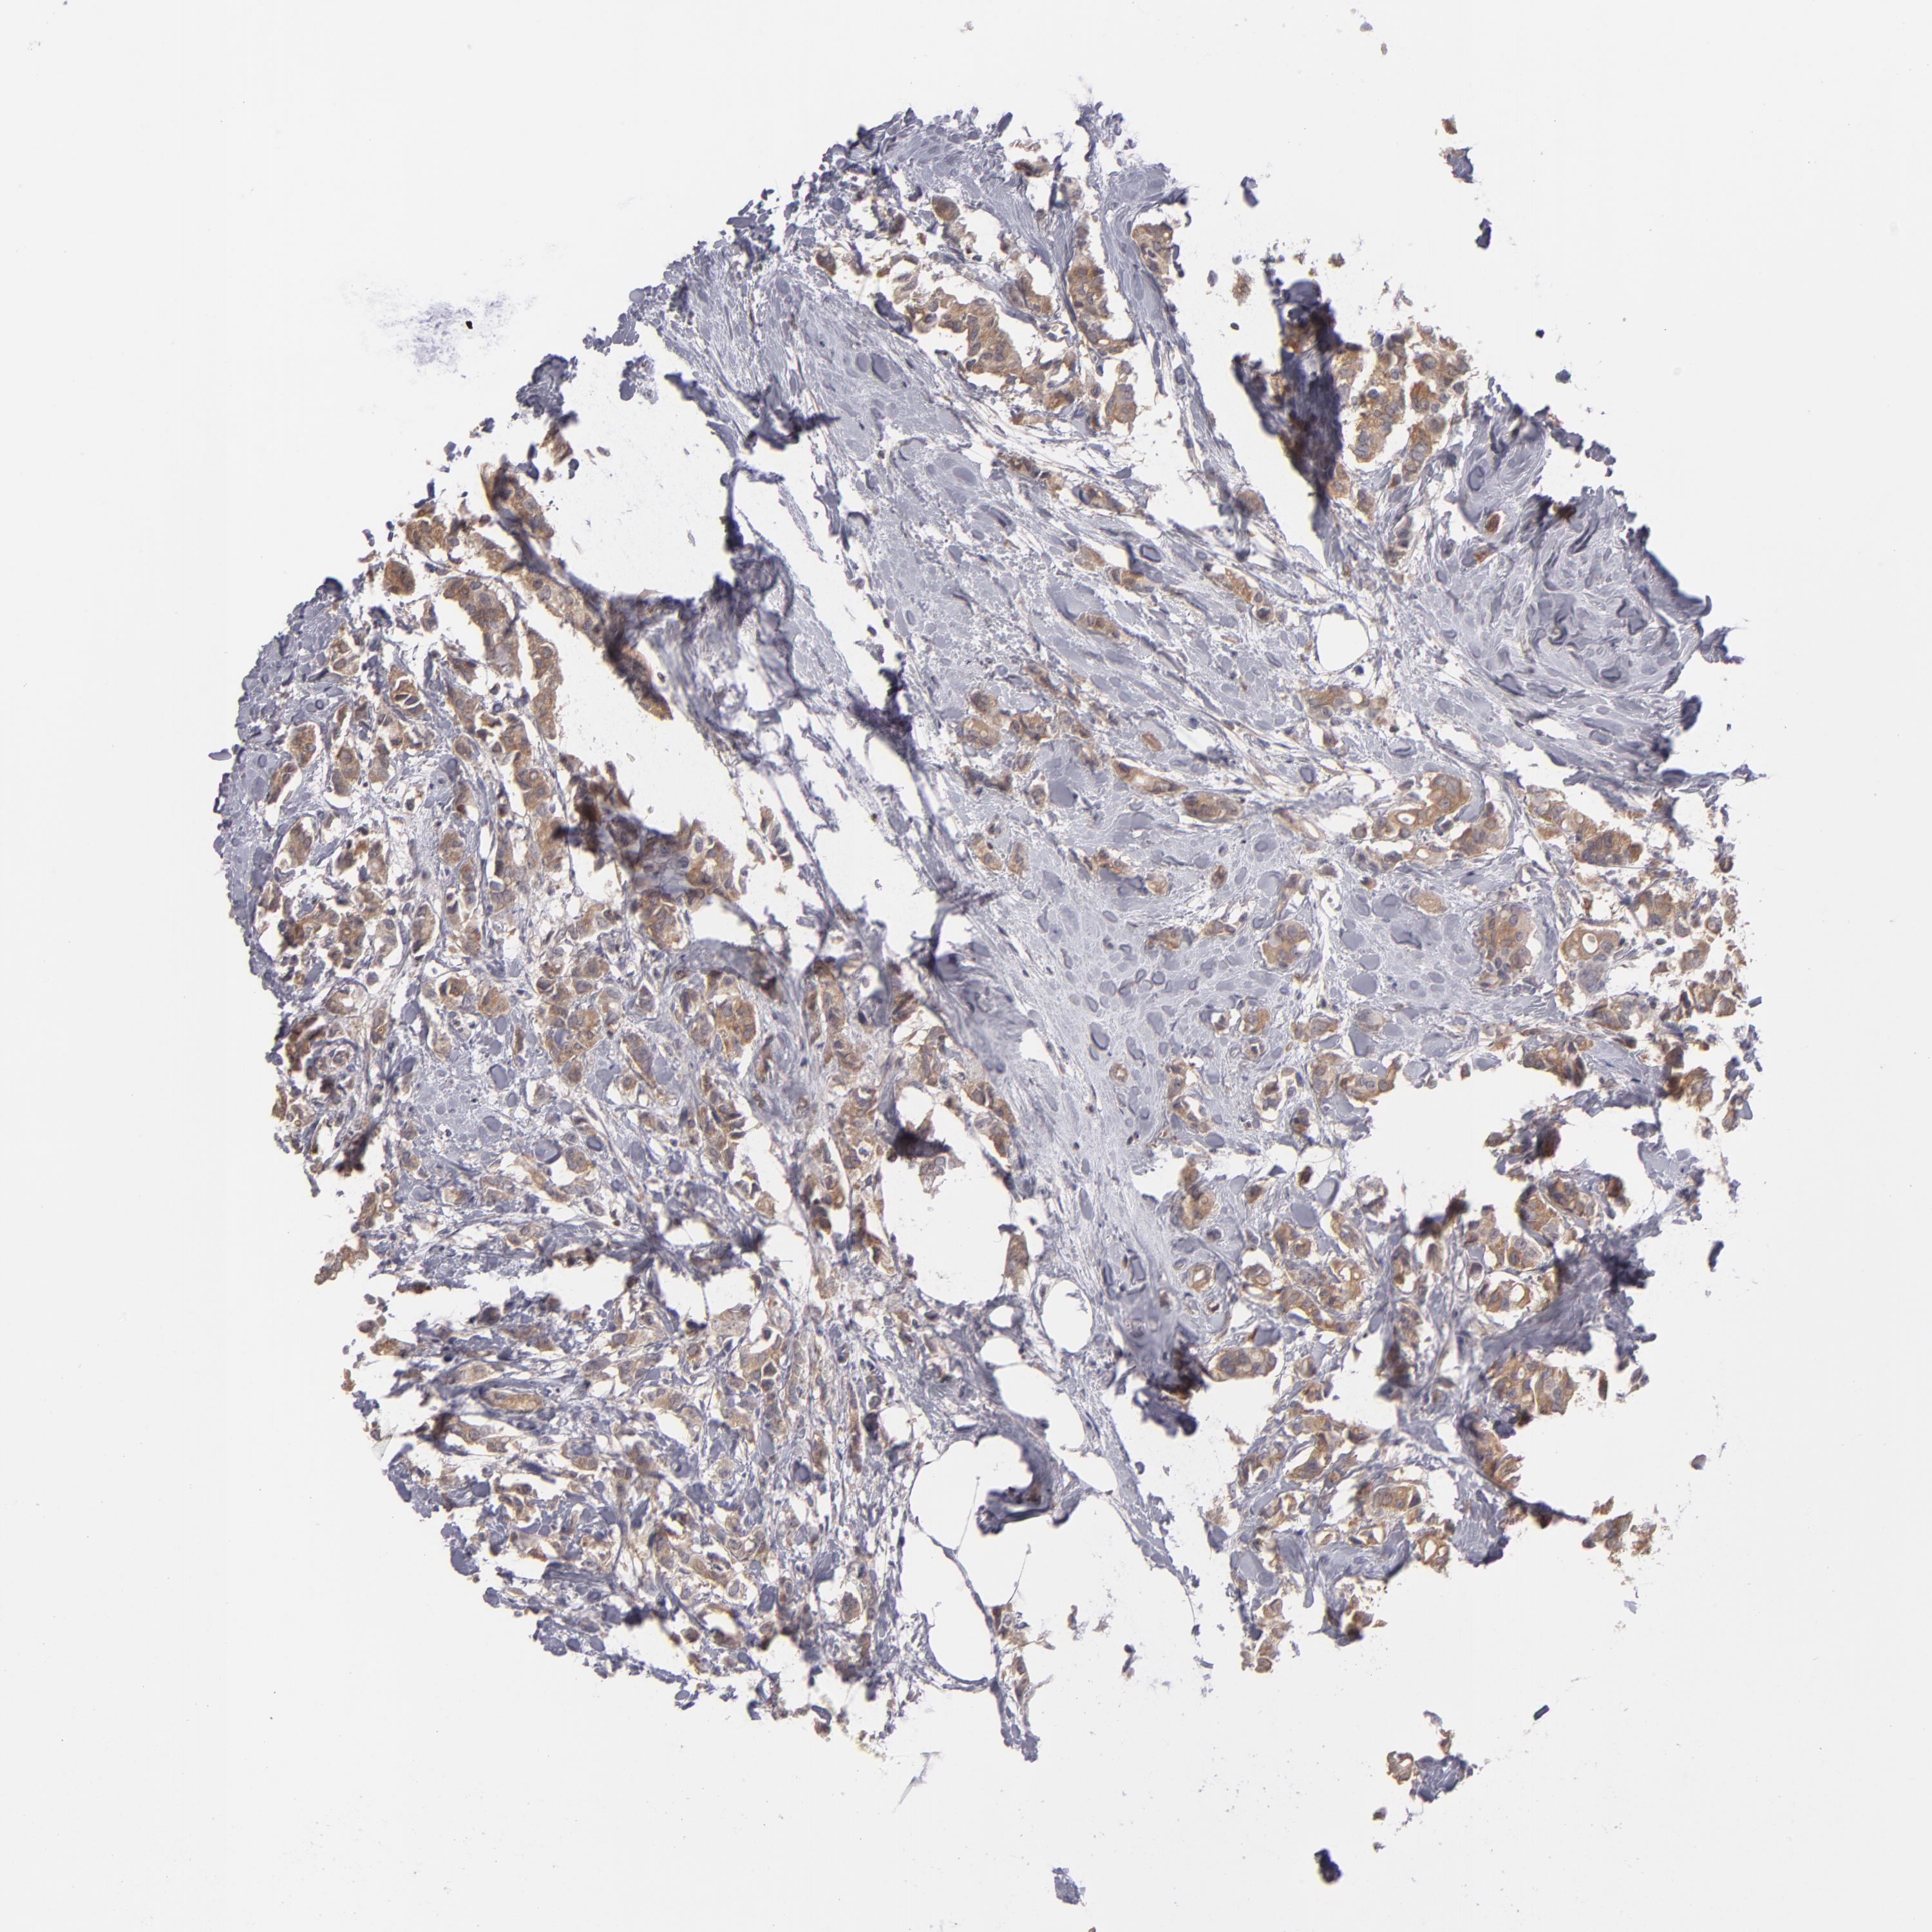

BRCA TCGA BRCA VALIDATION PROTEIN EXPRESSION

ANTIBODIES

AND

VALIDATION